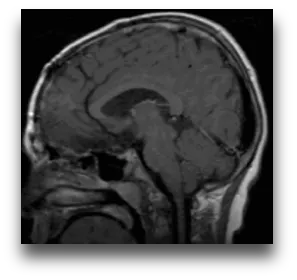

下面这个案例来自鲁特卡教授曾接诊过的一位9岁患儿。她因头痛及视野受限被诊断出一个巨大囊性颅咽管瘤,在经过VP分流术并植入Ommaya储液囊后,肿瘤体积明显缩小,在MRI上几乎看不到。